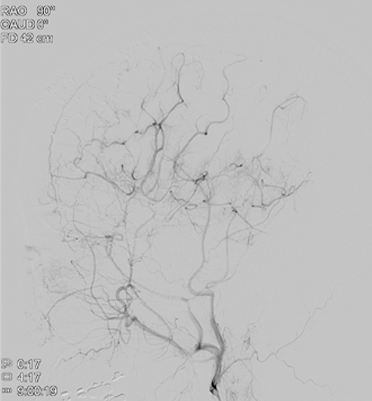

모야모야 뇌혈관 조영술 사진

두개내외 뇌혈관우회로수술, 수술 후 뇌혈관조영술 및 뇌관류CT